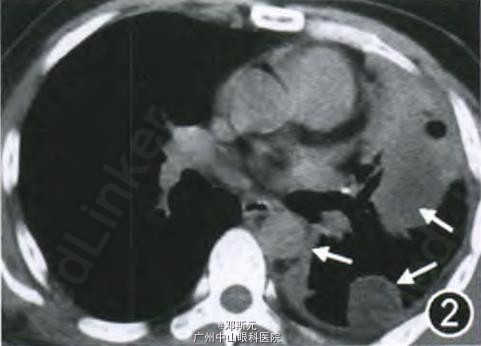

患者男,40岁,因“胸痛4个月”于2013年7月收入北京协和医院呼吸科。2013年3月患者无诱因出现双侧胸痛,呈持续性隐痛,与呼吸相关。胸部CT示右肺上叶小结节,左侧胸膜明显增厚及左肺下叶膨胀不全,左侧胸腔积液(图l,2),PET—CT示右肺上叶结节放射性摄取稍高,标准摄取值(SUV)为1.1,左侧胸膜多发结节状放射性摄取增高灶,SUV值为2.9,中下肺为著。胸腔穿刺抽出血性胸腔积液,为渗出性,未见癌细胞。2013年4月行“胸腔镜辅助右上肺结节切除术”,术后病理为“右上肺错构瘤(以软骨成分为主)”。但术后胸痛未缓解,且左侧胸痛加剧,复查胸部CT提示左侧胸腔积液增多。2013年6月行“左侧小开胸、粘连松解及胸膜病变切除活检术”,术中见胸膜结节状增厚并广泛粘连,胸膜腔闭锁,切取局部少许胸膜送检。术后病理示纤维脂肪组织,局灶轻度异型细胞增生;免疫组织化学染色细胞角蛋白AEI/AE3阳性,考虑间皮瘤不除外,未明确诊断。2013年7月行“经皮左侧胸膜穿刺活检术”,术后病理(结合患者上次开胸胸膜活检标本)示肿瘤细胞排列成小巢状,短索状,可见血管腔样裂隙,基质呈浅蓝色黏液透明样。肿瘤细胞呈上皮样或组织细胞样,圆形、多边形或梭形,胞质丰富,嗜伊红色,胞质内管腔或空泡形成不明显,瘤细胞核略呈空泡状,核仁及核异型性不明显,未见明确的核分裂相,未见实性梭形细胞区域或坏死。免疫组织化学染色示分化簇3l、分化簇34及波形蛋白阳性,第八因子相关抗原、CK5/6及钙视网膜蛋白阴性。符合EHE(图3~,为进一步治疗收入院。有长期吸烟史。